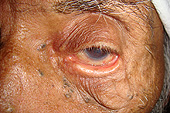

Patient with ectropion left lower lid (lid rolled out). This causes chronic blurred vision, dry eye, redness, recurrent infections, and eventually, scarring of the cornea and conjunctiva

Immediately after ectropion repair. Note that the lid is now higher and tighter. This improved anatomic position will better protect the eye. The redness and swelling will resolve within a week

Close-up, ectropion

Close-up, after repair